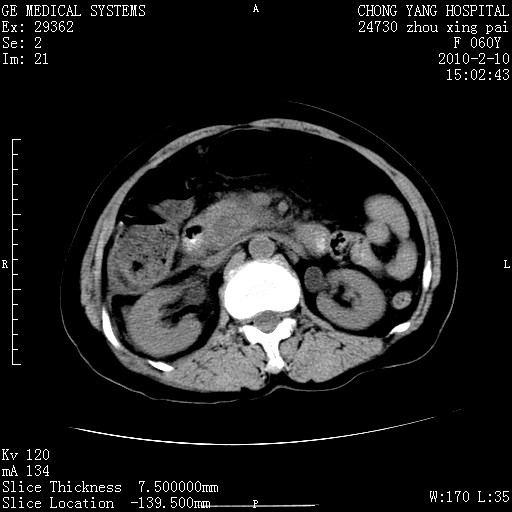

标题: CT24682:F60Y 腹痛 其它不详 [打印本页]

标题: CT24682:F60Y 腹痛 其它不详

胆总管末端梗阻!结石?胰腺影增粗,以胰腺头部为著,胰周看见渗出影,双侧胸腔积液,(胸膜反应)考虑胰腺炎。

1)胆总管末端梗阻,不排除结石所致可能。2)胰腺炎。3)慢性胆囊炎可能。4)左侧输尿管上段扩张。5)少量腹水。6)双侧少量胸腔积液,伴两下肺部分肺萎陷。

1)胆囊炎。2)胆源性胰腺炎。3)右肾周筋膜增厚,肾旁前间隙积液。4)左侧输尿管上段扩张。5)少量腹水。6)双侧少量胸腔积液,伴两下肺部分肺膨胀不全。

1)胆总管末端梗阻。2)胰腺炎。3)慢性胆囊炎可能。4)左侧输尿管上段扩张。5)少量腹水。6)双侧少量胸腔积液,伴两下肺部分肺萎陷。